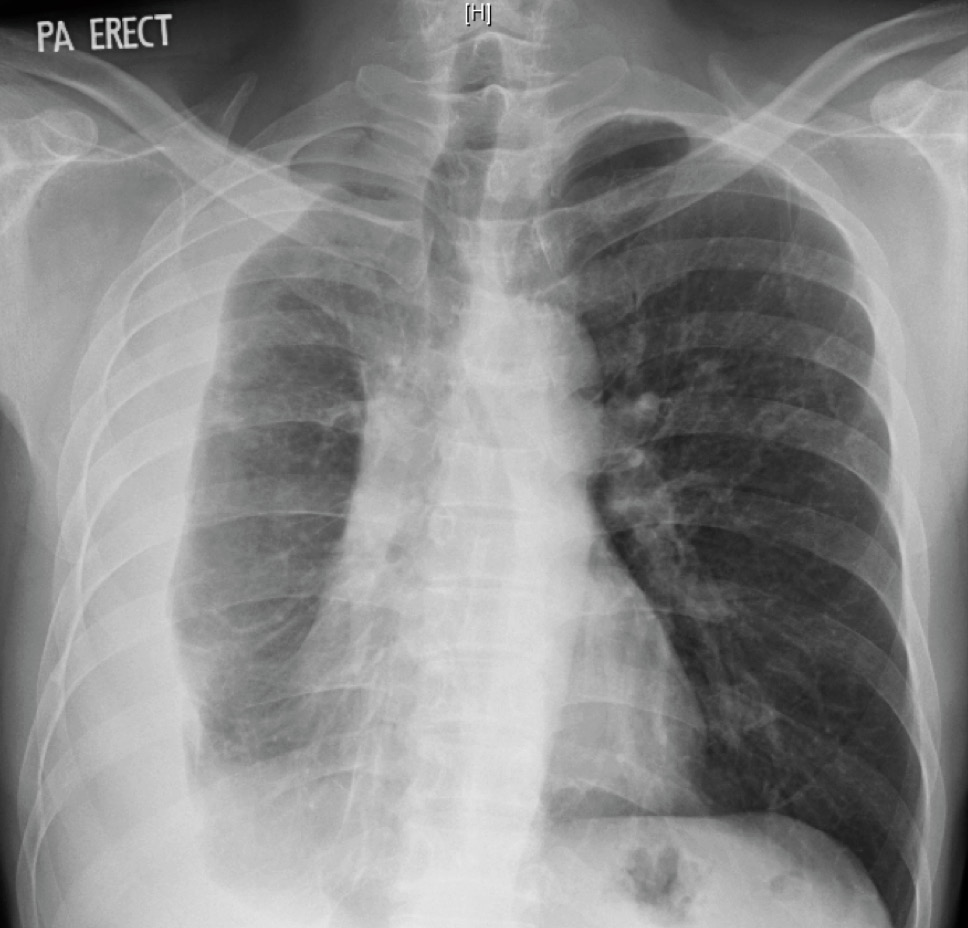

He felt clinically better after starting the anti-tuberculosis therapy, with no further fever nor shortness of breath (except on exertion), and had also started to gain weight. The pleural fluid culture was positive for Mycobacterium tuberculosis complex which was sensitive to all drugs. During the routine follow-up visit after completing 2 months of therapy, however, the chest X-ray was grossly abnormal.

Chest X-ray 2 months after starting anti-tuberculosis therapy, showing a massive right pleural effusion.